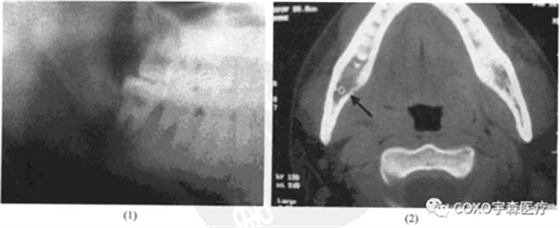

檢查:7] II度松動,81] III度松動,右頜下扣及1cm×1cm,質(zhì)地較軟,有壓痛之腫塊。X線片示:8]根尖區(qū)陰影;CT示:8]區(qū)骨髓腔稀疏,舌側(cè)骨板有蟲蝕樣破壞(圖13-12).

患者6年前在某市醫(yī)院被診斷為白血病(M3),治療后病情穩(wěn)定,現(xiàn)不服用藥物。收入本院口腔頜領(lǐng)面病房,局麻下拔除87]并行頜下腫塊活檢。病理報告:密集小細(xì)胞浸潤,細(xì)胞有異形,核分裂易見,考慮為白血病侵犯所致。后轉(zhuǎn)入本院血液病科,給予止血敏、輸血小板、凝血酶、抗生素等治療,癥狀消失,下頜腫塊顯著縮小。

患者因牙痛,夜間加劇,下唇麻木和局部出現(xiàn)腫塊而就診。X線攝片顯示:8]根尖陰影,因而首先考慮為根尖周病,但因有下唇麻木及腫塊存在又應(yīng)考慮頜骨中心性病損,特別是惡性腫瘤。再追問病史有白血病史,又不排除根尖周病的可能。為進(jìn)一步證實其病損的性質(zhì),拔牙后病理證實為白血病侵犯。

白血病系血液系統(tǒng)腫瘤,全身性疾病,各處均可首發(fā),以頜骨作為首發(fā)者極為罕見。本例初看不能排除牙髓根尖周病,但追問病史即可首先懷疑腫瘤;如忽視全身病史則很可能漏診或誤診。因此,牙體牙髓病??漆t(yī)師必須要有全身觀